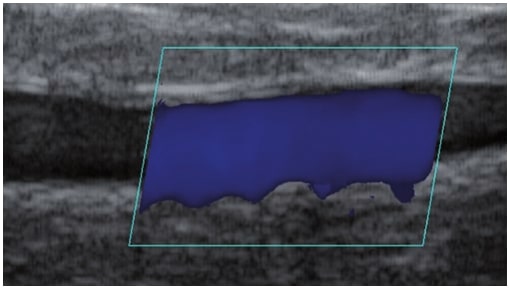

La ecografía Doppler permite obtener imágenes de grandes vasos y perforantes que suelen estar situados en las capas más profundas del tejido subcutáneo (fig. 1). Desgraciadamente, la ecografía convencional no es capaz de obtener imágenes de vasos más pequeños. Para visualizar los vasos más pequeños situados cerca de la superficie de la epidermis y en la capa superior del tejido subcutáneo, se utiliza el HFU (fig. 1). Gracias al uso de transductores con frecuencias superiores a 20 MHz, se obtiene una imagen ecográfica de alta resolución en la que podemos diferenciar estructuras menores de 0,1 mm. Sin embargo, cuanto mayor es la resolución, menor es la penetración del haz de ultrasonidos en las capas de la piel. Por lo tanto, dependiendo del transductor y del aparato, es posible penetrar en la piel hasta una profundidad de 20-30 mm como máximo. Tal penetración, junto con la alta resolución de la imagen, permite la evaluación incluso de vasos sanguíneos muy pequeños (fig. 2). Durante el examen con el uso de transductores de alta frecuencia, se puede evaluar con precisión el curso y la ubicación de los pequeños vasos en la piel. Esto es particularmente relevante para la selección del método de cierre del vaso y la planificación del procedimiento ya que, en la práctica, la superficie de la piel muestra muy a menudo únicamente un pequeño número de vasos o un ligero fragmento de un vaso; solo tras el examen por ecografía podemos determinar su número y curso reales. Para un cierre eficaz del vaso, es necesario hacerlo en toda su longitud. No debe limitarse al fragmento visto «a simple vista» en la superficie de la piel, ya que el cierre del fragmento causará su rápida recanalización(7). Con frecuencia, el vaso visible en la superficie de la piel cambia su curso, se vuelve más tortuoso y se desplaza a las capas más profundas de la piel(8). Por lo tanto, el curso de la vena y las perforantes deben conocerse y determinarse bien antes del procedimiento. El HFU también permite obtener imágenes de las perforantes entre pequeños vasos. Además, aparte de la evaluación del curso y la anatomía, la imagen ecográfica, gracias al software de ultrasonidos, también permite determinar los parámetros básicos como el diámetro del vaso, el grosor de su pared, la profundidad en la piel así como la presencia o ausencia de perfusión en el interior del vaso(6) (fig. 3). Gracias al transductor electrónico multielemento con la frecuencia de 40 MHz introducido en el mercado por Ultrasonix, también es posible visualizar la perfusión en los vasos en el modo Doppler color (fig. 4).